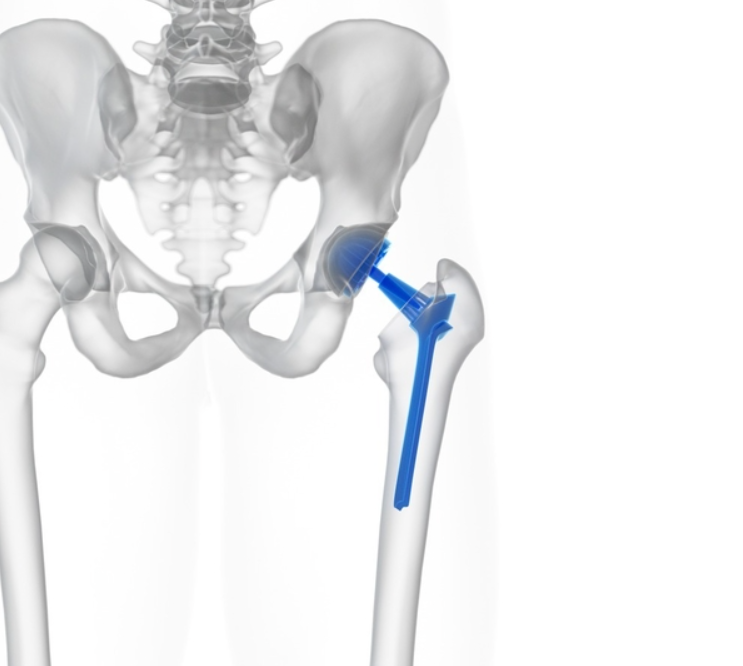

고관절재치환술은 이전에 시행한 인공관절 치환술 후 문제가 발생했을 때 다시 시행하는 치료입니다.

처음 받은 치환술이 시간이 지나면서 침강, 마모, 감염 등의 문제로 인해 통증이 재발하거나 다리 길이 차이가 생길 수 있습니다.

이런 경우 재치환술을 통해 손상된 부위를 교체하고 정상적인 보행 기능을 회복할 수 있습니다.

이런 경우 손상된 부위를 지나 더 깊은 곳에 고정할 수 있는 모듈형 롱 스템이 효과적입니다.

반복된 시멘트 고정 실패를 고려하여, 뼈에 직접 골유합이 일어날 수 있는 방식을 선택할 수 있겠죠.

텅 빈 뼈 내부 공간에는 동종골을 채워 넣어 향후 뼈가 재생될 수 있도록 섬세하게 조치합니다.